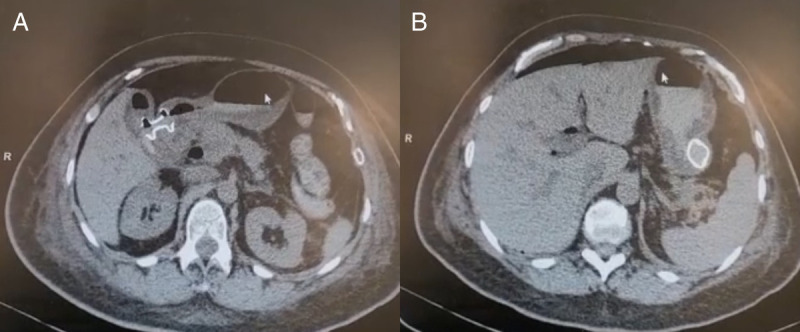

Double EUS-guided bypass for gastric outlet and biliary tract malignant obstruction: A standardized one-step approach (with videos).